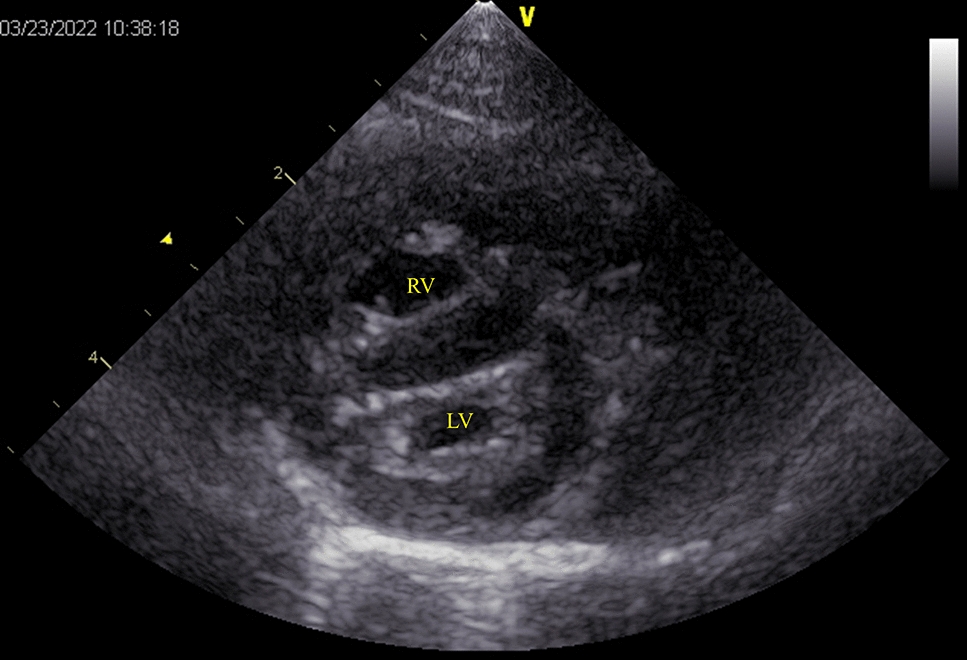

Case presentation: A 2 year-old Norwegian Forest cat was diagnosed with pulmonary oedema and PH secondary to cor triatriatum sinister (CTS) and showed improved breathing following two subcutaneous furosemide treatments, 1 and 2 mg/kg, during an overnight stay at the referral veterinary hospital. Sildenafil alone (0.69 mg/kg, PO, BID) was prescribed post-discharge to address PH without diuretics. Post-discharge from the referral veterinary hospital, collapse and pre-syncope were suspected to be due to PH. Consequently, sildenafil was titrated weekly, starting at 1.09 mg/kg BID and increasing to 1.63 mg/kg BID. Pre-syncope and collapse resolved, and pulmonary opacities reduced considerably, although concerns remained that increased pulmonary blood flow to suspected CTS from sildenafil might worsen cardiogenic pulmonary oedema. The patient was also treated with rivaroxaban (2.5 mg/head, SID), considering the increased risk of thrombus formation due to blood flow stasis and endothelial damage. Thirty-eight days later, the cat presented for the first time to our hosipital (Azabu University Veterinary Teaching Hospital) for examination. On echocardiography, a continuous mosaic blood flow (maximum and minimum velocity, 3.14 m/s; estimated pressure gradient, 39.4 mmHg) was observed in two enlarged pulmonary veins. Pulmonary artery enlargement (main pulmonary artery to thoracic aorta ratio: 1.90), pulmonary vein stenosis (PVS), and diffuse bilateral ground-glass lung opacities were observed using computed tomography. PH with unilateral PVS involving two out of the three right pulmonary veins, specifically the right cranial and right middle pulmonary veins, along with pulmonary parenchymal disease, was diagnosed. The cat was further treated with furosemide (1 mg/kg, BID, PO) with no clinical signs but succumbed to acute dyspnoea 51 days after the first visit.

背景:猫的肺动脉高压(PH)检测可能具有挑战性。肺静脉狭窄(PVS)在猫中很少见,可导致ph。唯一报道的PVS病例接受了尸检诊断。在猫的一生中成像确定了本病例的诊断。病例介绍:一只2岁的挪威森林猫被诊断为肺水肿和PH继发于心房三房性心脏病(CTS),在转诊兽医医院过夜期间,两次皮下速尿治疗(1和2 mg/kg)后呼吸改善。出院后单独开西地那非(0.69 mg/kg, PO, BID)处理PH,不使用利尿剂。从转诊兽医院出院后,怀疑是ph引起的晕倒和晕厥前期。因此,每周滴定西地那非,从1.09 mg/kg BID开始,增加到1.63 mg/kg BID。晕厥前期和虚脱消退,肺混浊明显减少,尽管仍然担心西地那非导致疑似CTS的肺血流量增加可能加重心源性肺水肿。考虑到血流停滞和内皮损伤导致血栓形成的风险增加,患者还接受了利伐沙班治疗(2.5 mg/头,SID)。38天后,猫首次到我院(麻布大学兽医教学医院)检查。超声心动图显示连续的马赛克血流(最大和最小速度为3.14 m/s;估计压力梯度,39.4 mmHg)。ct示肺动脉扩张(主肺动脉与胸主动脉比值:1.90),肺静脉狭窄(PVS),双侧弥漫性磨玻璃肺影。诊断为PH伴单侧PVS累及右肺三条静脉中的两条,特别是右颅静脉和右中肺静脉,同时伴有肺实质疾病。猫进一步给予速尿(1 mg/kg, BID, PO)治疗,无临床症状,但在第一次就诊后51天出现急性呼吸困难。结论:局部肺泡型且无左房扩大的幼猫应考虑单侧PVS,因为预后可能较差。严重PH伴PVS可与肺部疾病共存。如果使用西地那非,应以低剂量开始并密切监测。